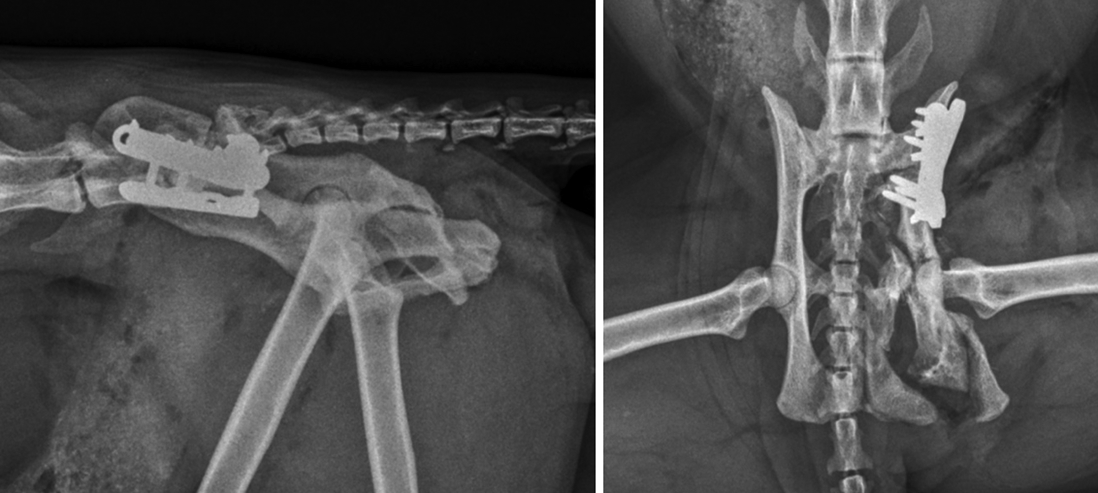

DT was used to identify the site of most significant pelvic canal diameter loss to determine the optimal approach for surgical widening of the pelvis. In addition to confirming pelvic fracture malunions (Figure 3), the DT image stacks demonstrated the exact site of severe narrowing of the colon and rectum at the level of the narrowing in the pelvis (Figure 4).

Somewhat surprisingly, the majority of pelvic canal stenosis, as identified by colon and rectum narrowing, did not appear to be associated with bone deformities.

Stenosis was largely associated with non-mineralised material within the pelvic canal. A generous mass of fibrocartilaginous callus within the pelvis was suspected. Additionally, surgical planning was aided by the appearance of a right obturator foramen, which was almost entirely occluded by the presence of the cranial aspect of the right ischium (Figure 5).

The obturator foramen is an important landmark in TPO, since two of the osteotomies (that of the pubis and the ischium) extend into this foramen. The narrowing of the pelvic canal and the level at which this was most severe was more clearly appreciable from the DT stack.

To address megacolon associated with pelvic stenosis refractory to non-surgical management, surgery was performed by triple pelvic osteotomy. Transverse osteotomies of the right pubis and ischium were performed through standard approaches. Performance of these osteotomies was complicated by both bones demonstrating remodelling, resulting in inadvertent release of a portion of the right ischium (including the ischiatic tuberosity) and a rather laterally located pubic osteotomy, close to, but not penetrating, the ventral acetabulum.

A transverse osteotomy of the right ilium was performed just caudal to the sacroiliac joint, and the right hemipelvis was translated abaxially. Fixation of the ilial osteotomy was with a laterally positioned 2.4mm locking tibial plateau-levelling osteotomy plate and screws – as previously described for fixation of ilial fractures by Guthrie and Kalff, 2018 – and a second parallel 2mm locking plate and screws. Postoperative plain radiographs were acquired after digital rectal palpation of the pelvic canal confirmed a significant increase in the pelvic canal diameter (Figure 6).